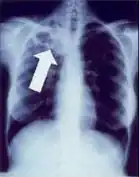

2. Any cavitary lesion - Lucency (darkened area) within the lung parenchyma, with or without irregular margins that might be surrounded by an area of airspace consolidation or infiltrates, or by nodular or fibrotic (reticular) densities, or both. The walls surrounding the lucent area can be thick or thin. Calcification can exist around a cavity.

4. Pleural effusion - Presence of a significant amount of fluid within the pleural space. This finding must be distinguished from blunting of the costophrenic angle, which may or may not represent a small amount of fluid within the pleural space (except in children when even minor blunting must be considered a finding that can suggest active TB).

5. Hilar or mediastinal lymphadenopathy (bihilar lymphadenopathy) - Enlargement of lymph nodes in one or both hila or within the mediastinum, with or without associated atelectasis or consolidation.